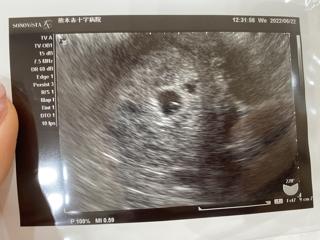

初診のエコー写真です。 この頃はまだ双子だということが判明していませんでしたが、次の検診の9w4dに先生から「2つあるから双子だね」と言われてびっくりしました。